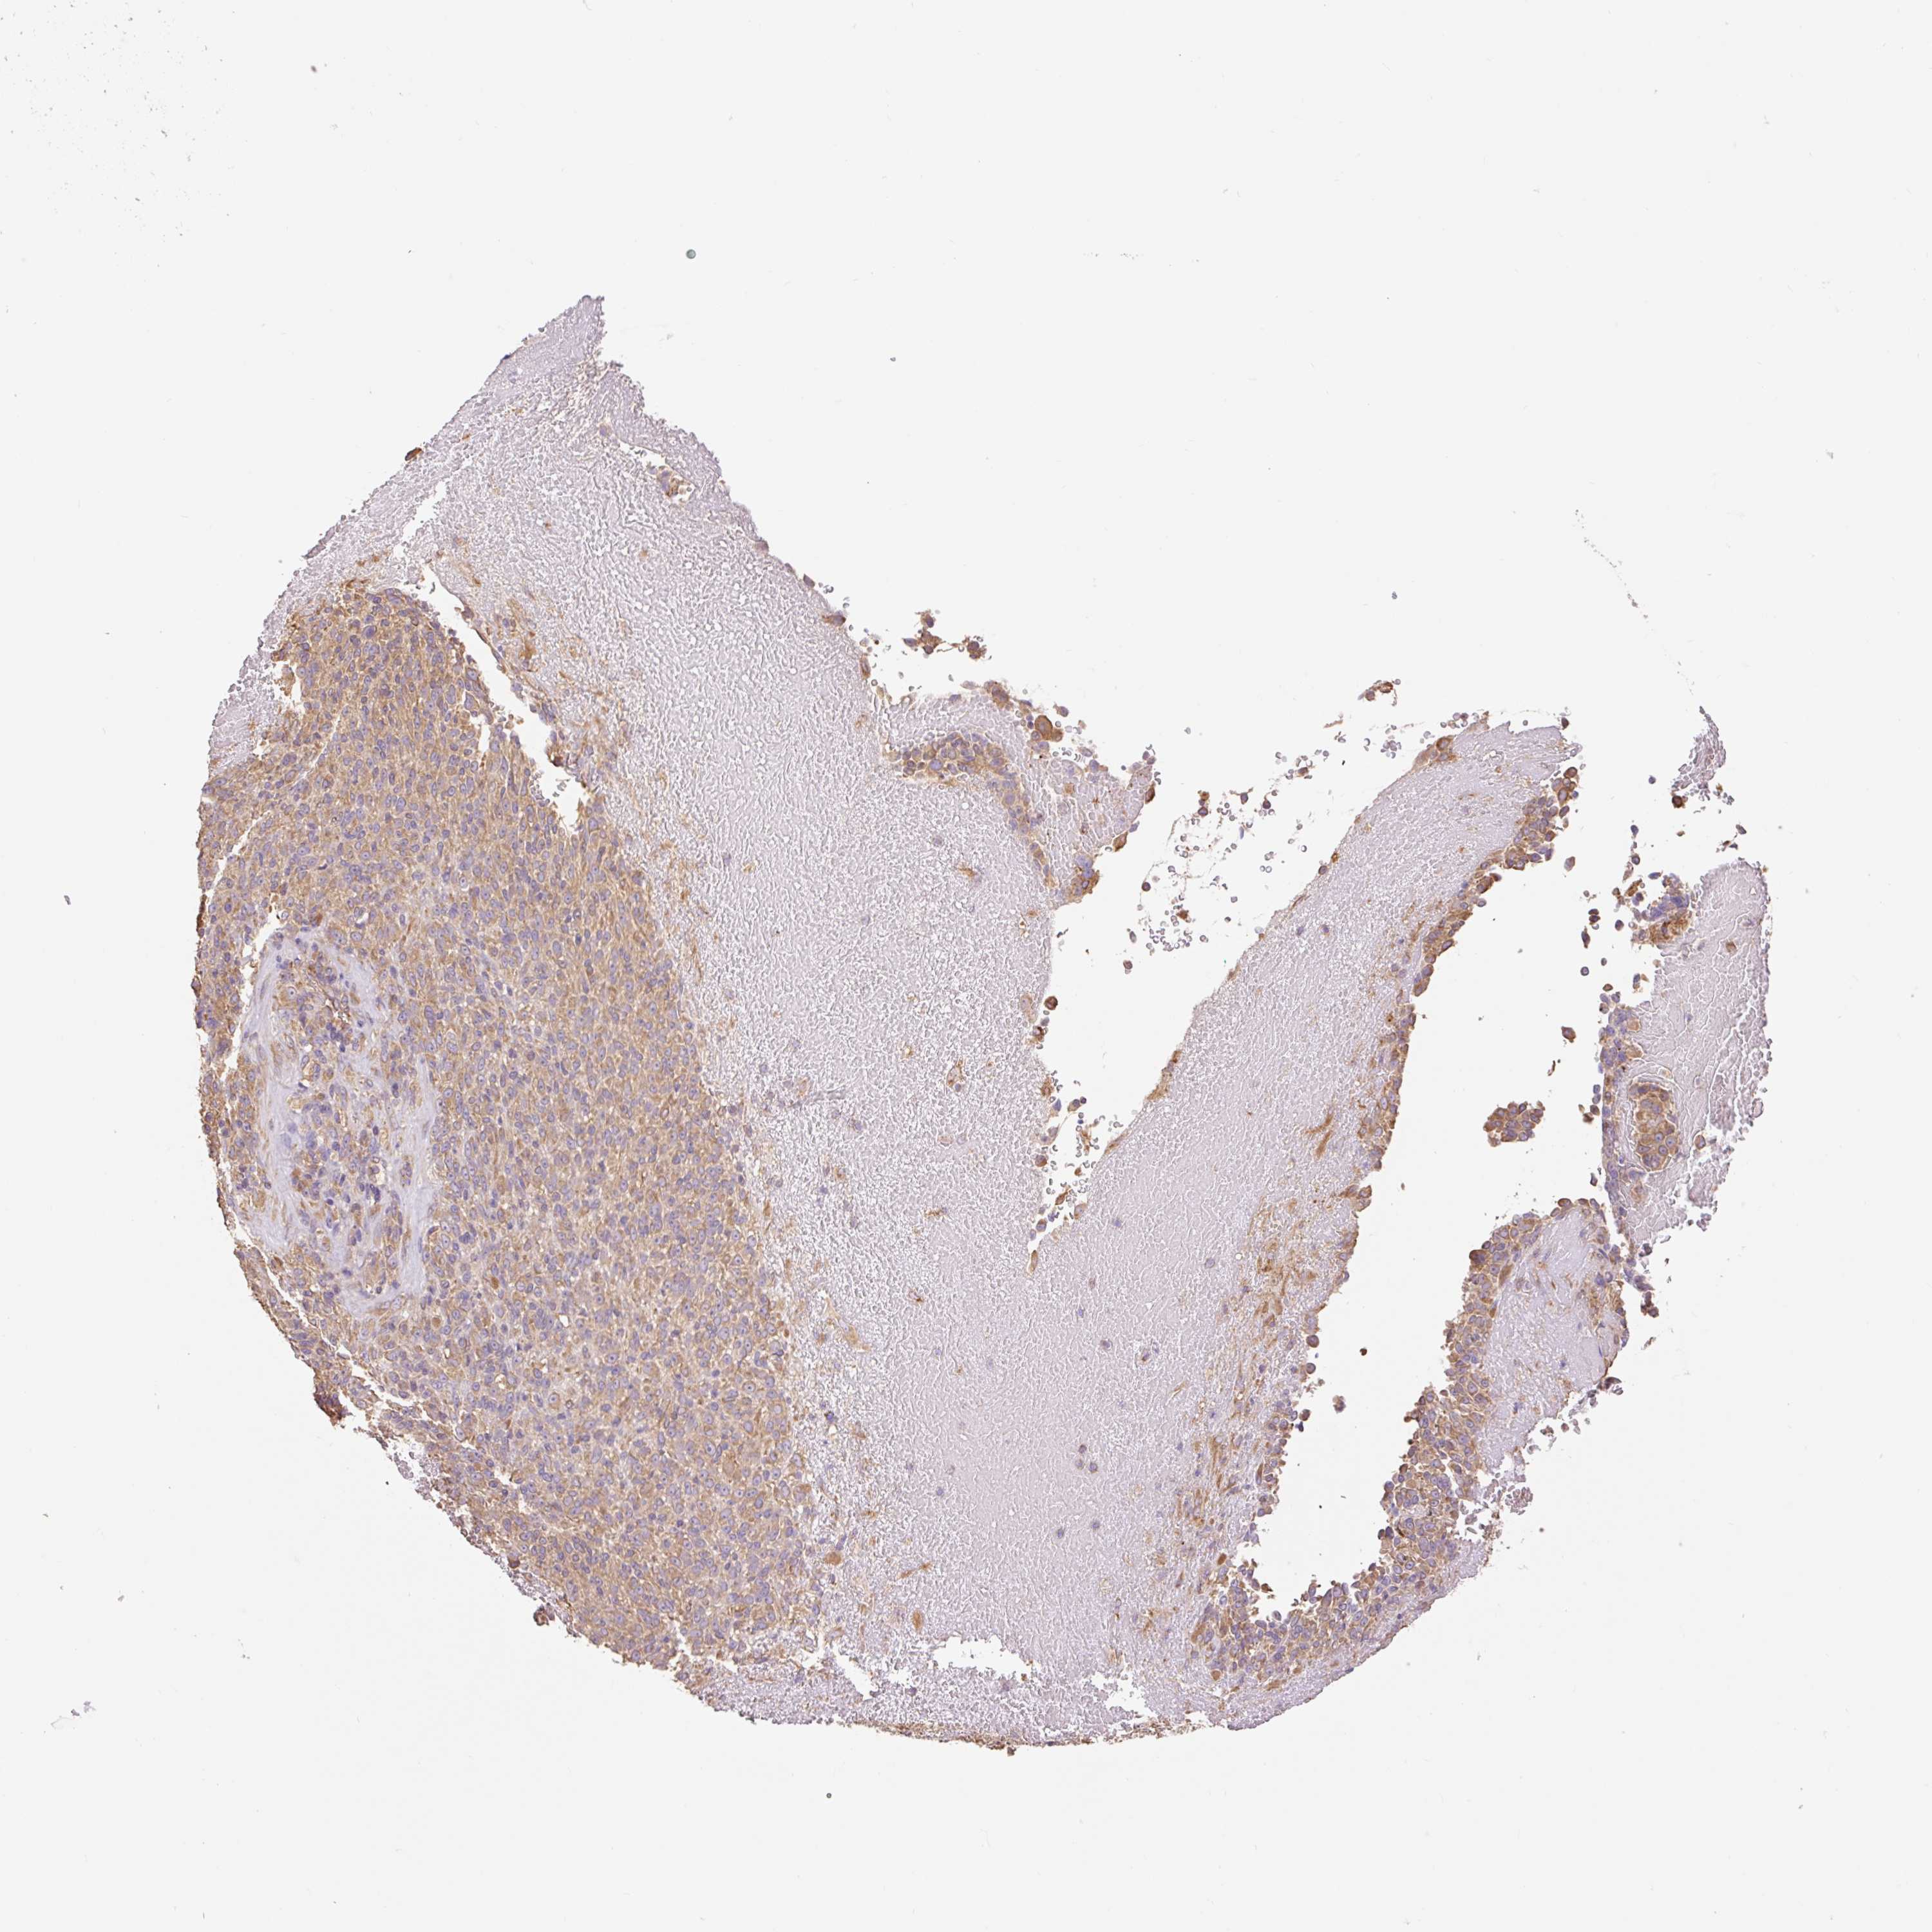

MELANOMA - Protein expressioni

A mouse-over function shows sample information and annotation data. Click on an image to view it in a full screen mode. Samples can be filtered based on level of antibody staining by selecting one or several of the following categories: high, medium, low and not detected. The assay and annotation is described here.

Note that samples used for immunohistochemistry by the Human Protein Atlas do not correspond to samples in the TCGA dataset.

Antibody stainingi

Antibody staining in the annotated cell types in the current human tissue is reported as not detected, low, medium, or high, based on conventional immunohistochemistry profiling in selected tissues. This score is based on the combination of the staining intensity and fraction of stained cells.

Each image is clickable and will lead to virtual microscopy that enables deeper exploration of all samples and also displays staining intensity scores, fraction scores and subcellular localization as well as patient and tissue information for each sample.

Antibody HPA053415

Staining

High

Medium

Low

Not detected

Intensity

Strong

Moderate

Weak

Negative

Quantity

>75%

75%-25%

<25%

None

Location

Nuclear

Cytoplasmic/membranous

Cytoplasmic/membranous,nuclear

Malignant melanoma, NOS